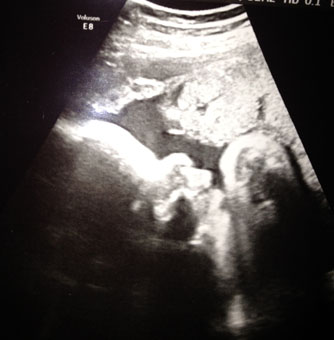

Jag vet inte om det var någon som höll tummarna där ute men det fungerade :)

Vi fick se tydliga bilder på en "liten" flicka :)Vad man kan se är allt som det ska vara förutom att hon redan nu väger 2,8 (i vecka 32)... Följer hon deras kurvor kommer det att bli en liten rulta på lite över 5 kilo :/. Klart lite orolig blir man men de trodde även att Dante skulle bli jätte stor. Och visss

Nästa vecka ska jag på sista ultraljudet då får ni hålla tummarna att de kan se om det blir en liten flicka eller pojke och att allt är bra med bebisen förstås.